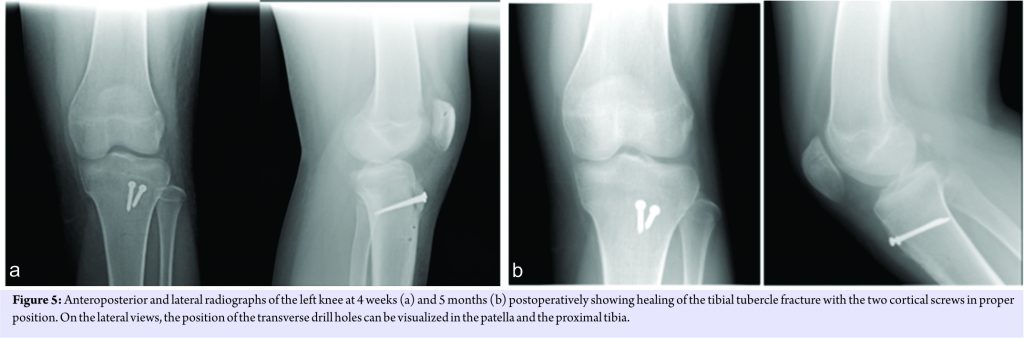

Final intraoperative fluoroscopic images were then obtained (Fig. 4). The wound was irrigated, the tourniquet was deflated, hemostasis was achieved, and a multilayered closure was performed. The remaining extensor mechanism tissue was repaired using 2-0 Ethibond in a figure-of-eight fashion, the deep soft tissue layers were approximated using 0vicryl, and the dermis and epidermis were approximated using 3-0 and 4-0 monocryl, respectively. Postoperatively, the left leg was placed into a knee immobilizer for the 1st week during full weight-bearing, and only taken out of the immobilizer to allow passive range of motion with up to 60° of flexion. After 1 week, a hinged knee brace was used to allow full weight-bearing and active range of motion up to 60°, and physical therapy was initiated for range of motion exercises. At 4-week follow-up, radiographs of the knee demonstrated interval healing of the tubercle fracture (Fig. 5), and range of motion was advanced to 90°of flexion in the hinged knee brace.3-month postoperatively, the brace was discontinued, and at the 5-month follow-up visit and the patient had active knee range of motion from 0° to 130° with no clinically significant extensor lag